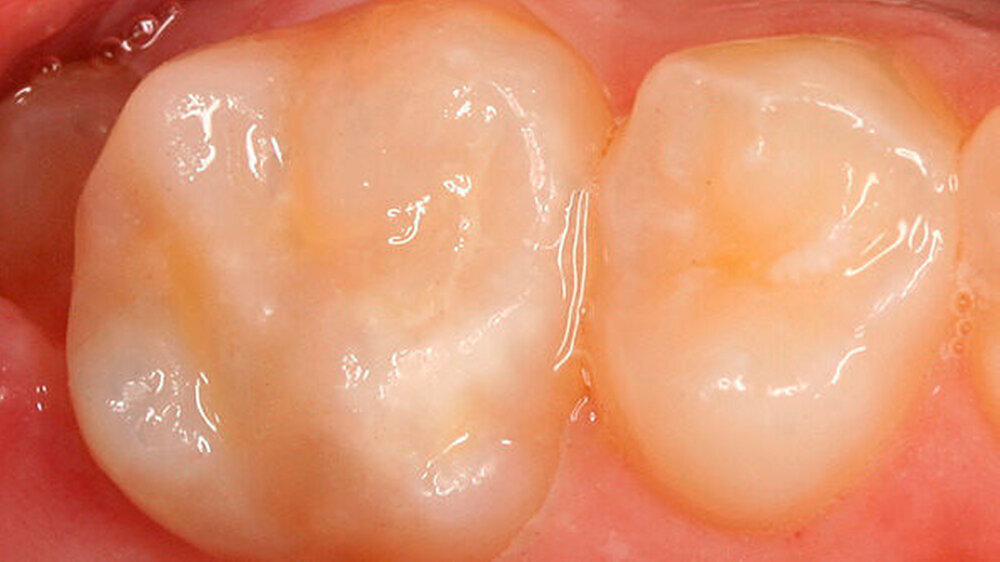

Die Patientin wies ein frühes Wechselgebiss auf, bei dem die Sechsjahr-Molaren, die gesamte Unterkieferfront und die oberen mittleren Inzisivi durchgebrochen waren. Der Zahn 54 hatte eine okklusal-distale Füllung, der Zahn 16 einen okklusal-distal-palatinalen Aufbau (Abbildung 1).

Zusätzlich zeigte der mesio-palatinale Höcker einen deutlichen Schmelzeinbruch (Abbildung 1). Die generelle Mundhygiene war nur mäßig, da insbesondere an den Glattflächen (obere mittlere Inzisivi) auch ohne Anfärbung deutlich sichtbarer Biofilm aufzufinden war (Abbildung 2). Die Zähne 26, 36 und 46 wiesen kaum sichtbare Opazitäten auf, sie waren alle versiegelt (nicht dargestellt).